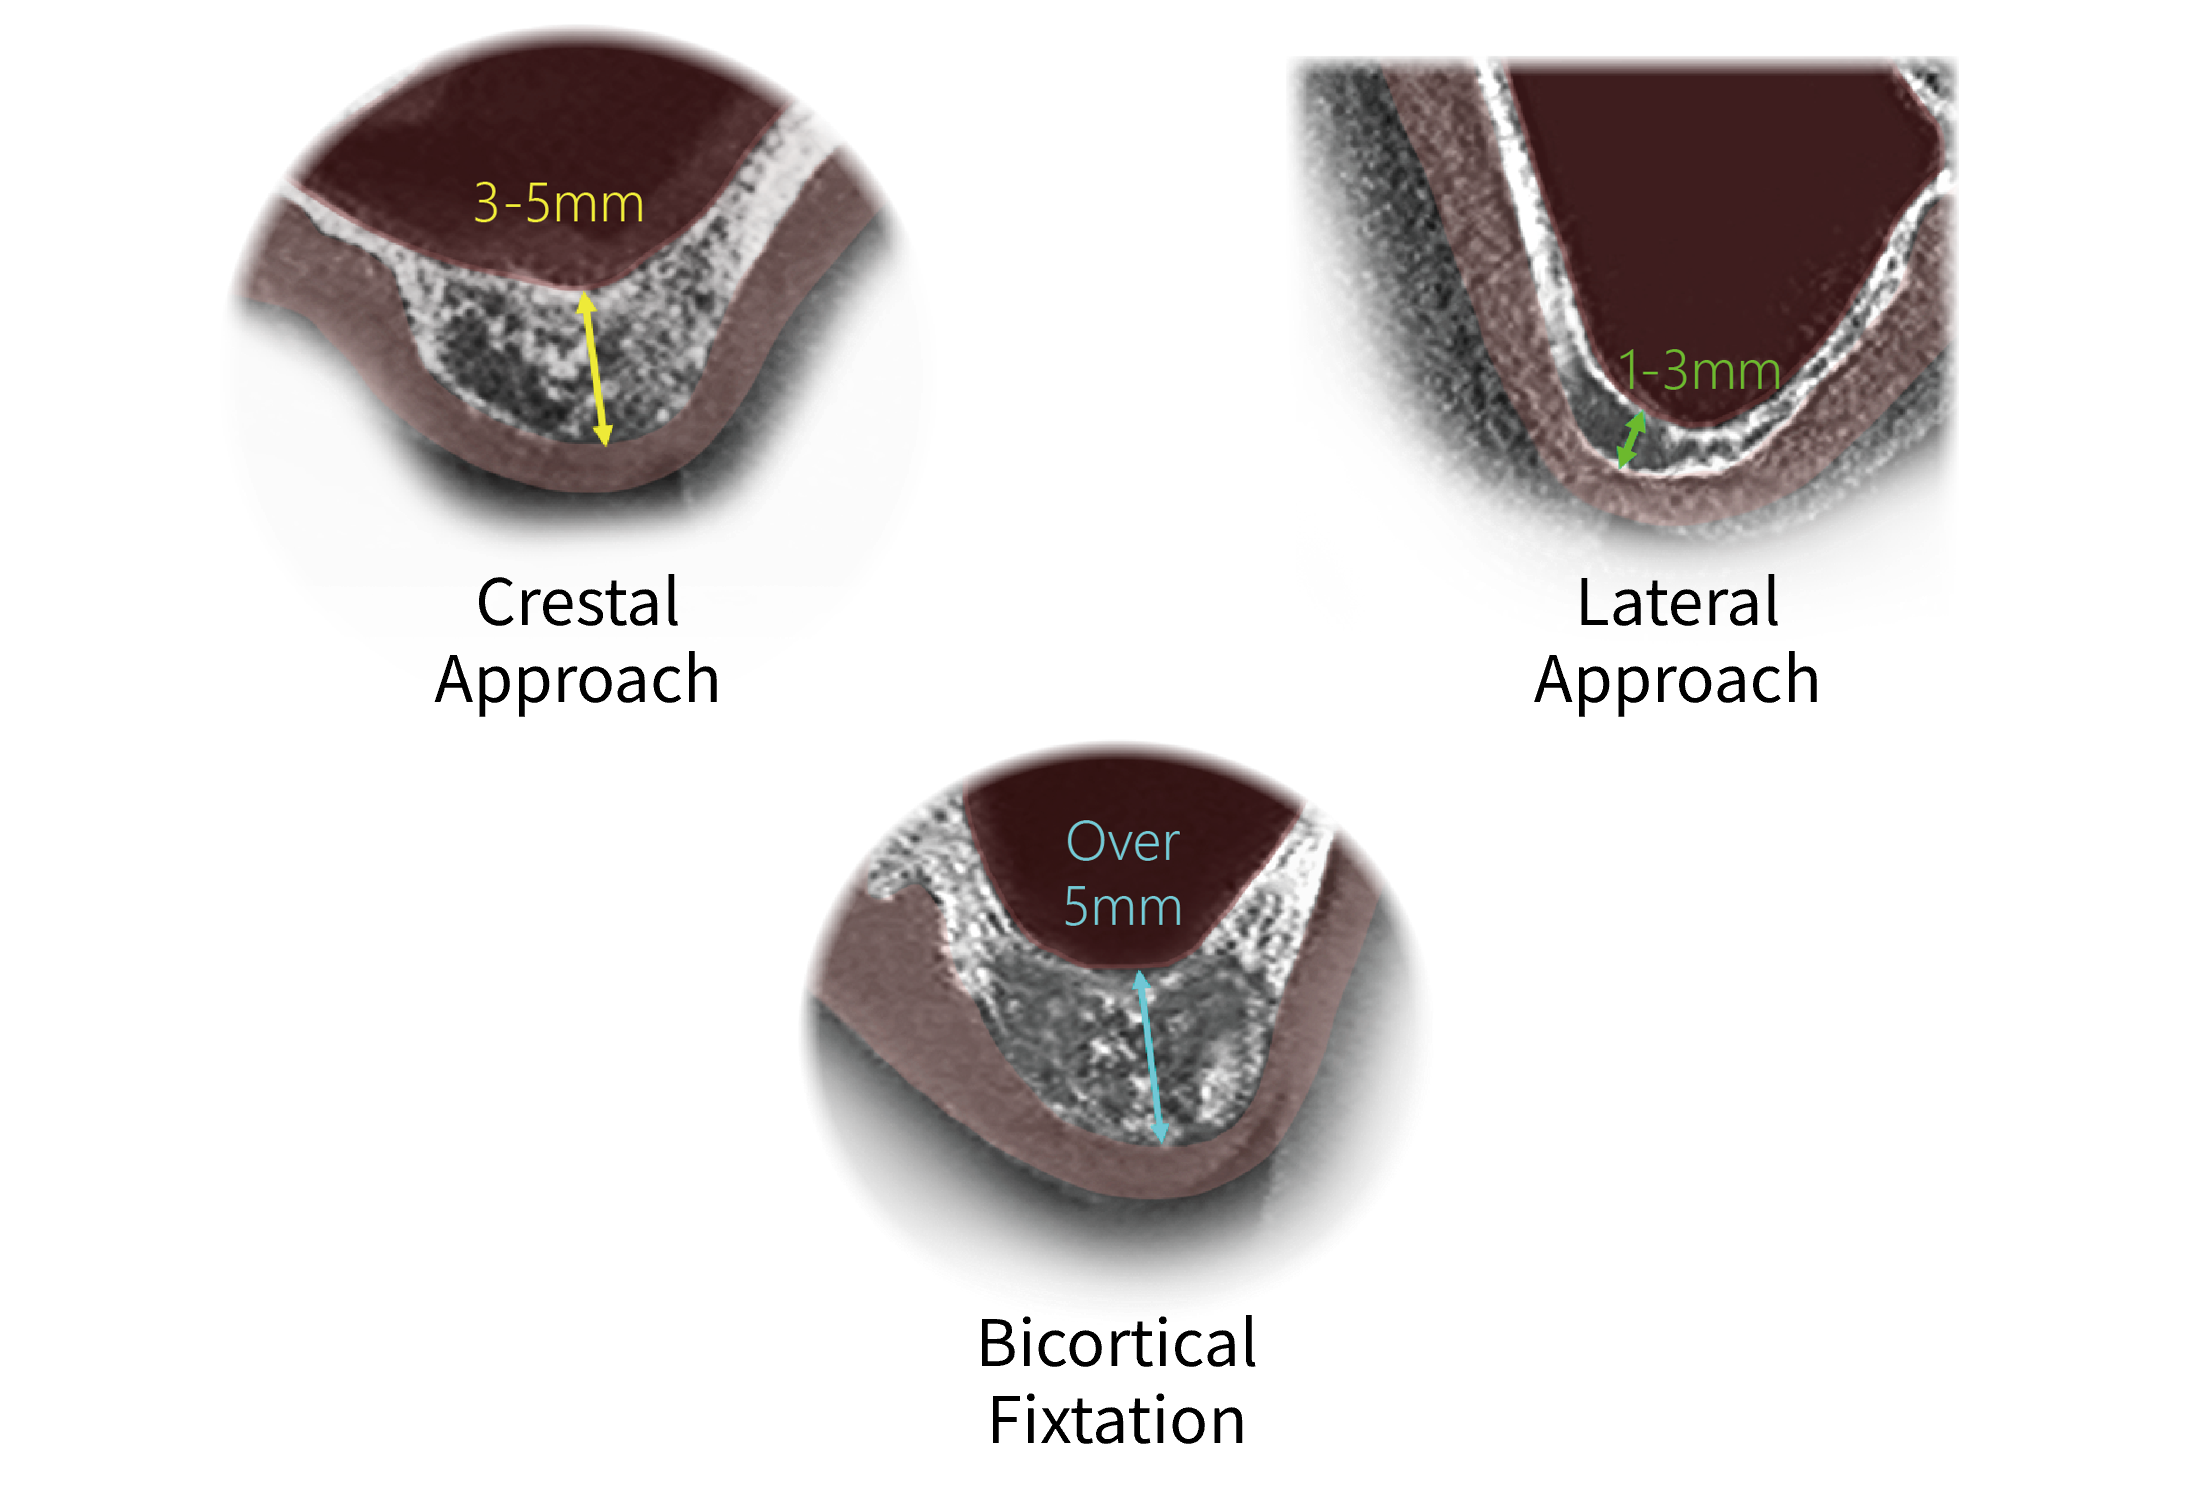

One Kit, Multiple Surgical ApproachesSupports lateral and crestal approaches, as well as bicortical fixation. One kit enables multiple surgical techniques without changing systems.

Bicortical FixationThe fastest and simplest approach for cases with remaining bone height of 5 mm or more.

Crestal ApproachAn efficient and safe approach that can serve as an alternative to the conventional lateral approach.

Lateral ApproachA flexible approach that allows access from multiple angles, even in severely limited bone conditions.